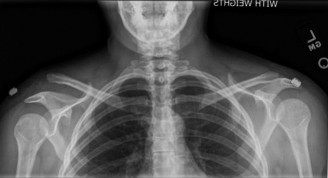

Your ultimate guide to Right Shoulder Pain? Avoid This Common X-ray Mistake. starts here. For acute right shoulder pain following a fall with limited range of motion, and an initial AP X-ray, the next most appropriate step is to obtain an axillary view x-ray. A single AP view is insufficient to conclusively rule out a fracture or a shoulder dislocation, which an axillary view helps to diagnose, guiding proper management.

The evaluation of acute shoulder trauma in the emergency department (ED) or urgent care setting is fraught with diagnostic pitfalls, the most egregious of which is the reliance on a single anteroposterior (AP) radiograph. As demonstrated in the clinical scenario of a 33-year-old male presenting after a traumatic sports injury, the acceptance of an isolated AP view is a cardinal error in orthopedic surgery. True orthogonal projections are non-negotiable. The axillary lateral view, or a modified trauma axillary (Velpeau) view, is absolutely critical to accurately assess glenohumeral concentricity. Failure to obtain this view routinely leads to missed posterior dislocations—often masquerading as the deceptive "lightbulb sign" on an AP view—as well as missed anterior subluxations, surgical neck fractures, and lesser tuberosity avulsions. The axiom remains: one view is no view.

Thorough pre-operative planning begins with advanced imaging. While the initial ED evaluation mandates true orthogonal radiographs (AP and Axillary views) to confirm joint concentricity and rule out fractures, definitive surgical planning requires cross-sectional imaging. Magnetic Resonance Imaging (MRI), preferably an MR Arthrogram with intra-articular gadolinium, is the gold standard for evaluating the soft tissues. It allows for the precise identification of Bankart, ALPSA, and SLAP lesions, assesses the volume and integrity of the capsular tissue, and evaluates the rotator cuff.

Clinical & Radiographic Imaging Archive